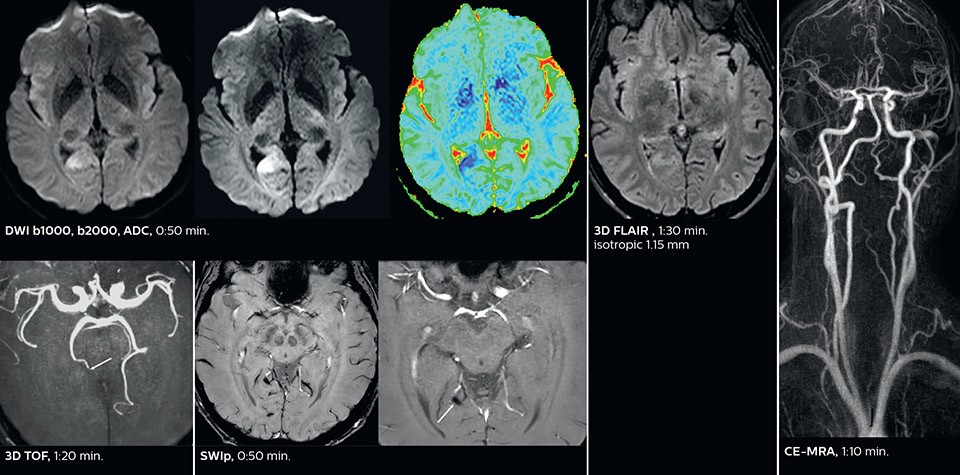

The ability to perform more sequences can help in making a swift and confident diagnosis. “For example, our stroke cases usually include the regular sequences that every center does (b1000 diffusion, FLAIR, time-of-flight angiography), but we also image supra aortic vessels, and we can replace a gradient echo sequence with a fast 50-second susceptibility-weighted sequence, and all of this doesn’t add much time. because all the regular sequences are accelerated on Elition.”

Fast acute stroke protocol

This is an example of acute ischemic stroke with distal occlusion of the right posterior cerebral artery. Note the improved visibility of the ischemic territory on the diffusion weighted image with high b-value. The 3D FLAIR shows a distal PCA occlusion. The fast SWIp depicts the thrombus on the isolated second echo image. The total scan time (including SmartBrain, preparations and a fast 3D T1w TSE Gd) is 8:00 minutes.